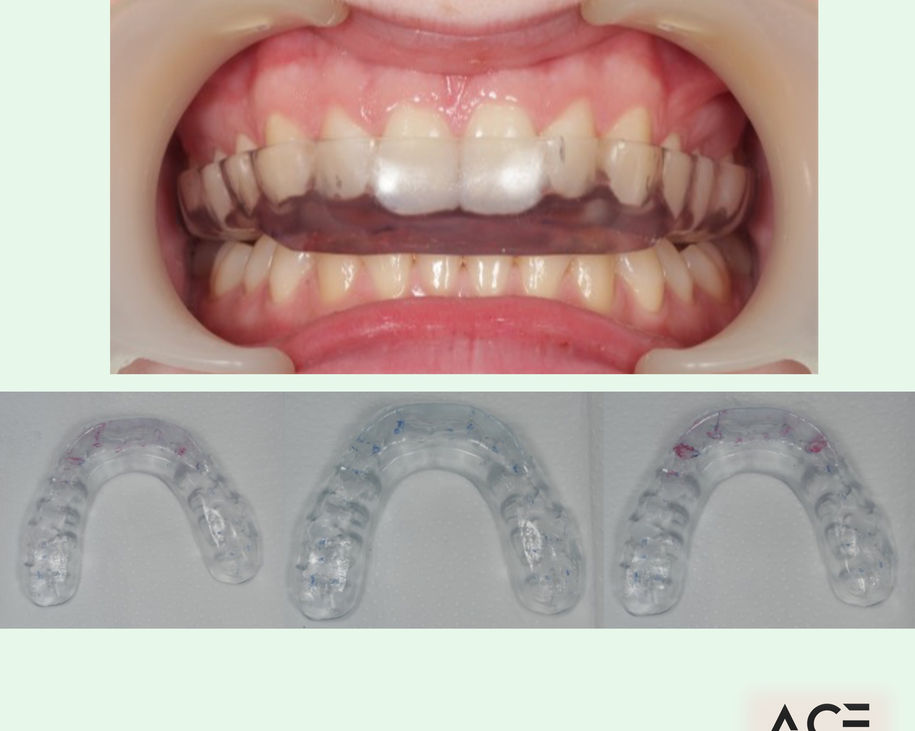

Alumni Outcomes showcasing below snippets of cases submitted as part diploma submissions

Dentists transitioning from routine dentistry into advanced restorative cases

Improved treatment planning confidence

Predictable clinical outcomes through structured protocols